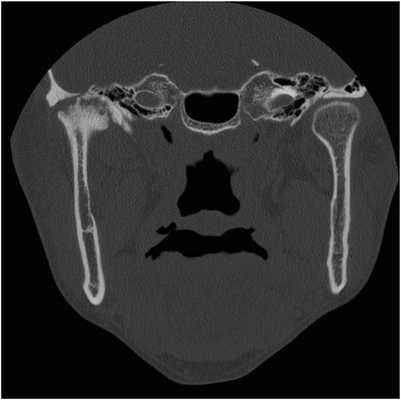

53-летняя женщина с ревматоидным артритом руки, запястья и плеча, обратилась за помощью по причине болевых ощущений в обоих ВНЧС. Она страдала от ревматоидного артрита в течение 1 года и принимала противовоспалительные препараты. КТ-диагностика подтвердила ревматоидное поражение обоих ВНЧС (фото 3а). У пациентки отмечалось ограниченное открывание полости рта (максимально до 23 мм), а болевые ощущения усиливались при движениях нижней челюсти. Для облегчения болевых симптомов было начато изготовление шины и проведен артроцентез обоих ВНЧС. Симптомы улучшились, однако у пациентки медленно начал развиваться передний прикус. Вертикальное перекрытие изменилось от начальных -6 мм до 0 мм (фото 3b).

Фото 3.

а) КТ-срезы, демонстрирующие сплющивание суставных головок, нерегулярность суставной поверхности и сужение суставных пространств.

b) Передний открытый прикус, который раздвинулся во время лечения с использованием шины.

с) Закрытие переднего открытого прикуса без прогрессирования нарушения в будущем.

Чтобы предотвратить прогрессирование патологии, была запланирована реконструкция ВНЧС. Во время операции было выполнено заднее перемещение верхней челюсти посредством остеотомии по Le Fort I, поскольку верхние передние зубы пациентки находились в состоянии протрузии. После резекции обоих мыщелков реконструкция ВНЧС с использованием протеза проводилась посредством вращения нижней челюсти против часовой стрелки для закрытия переднего открытого укуса (фото 3с). С момента операции на данный момент прошло уже 2 года, и в данный период не было отмечено никаких признаков воспалительного поражения области вмешательства. Симптомов прогрессирования открытого прикуса также не наблюдалось.